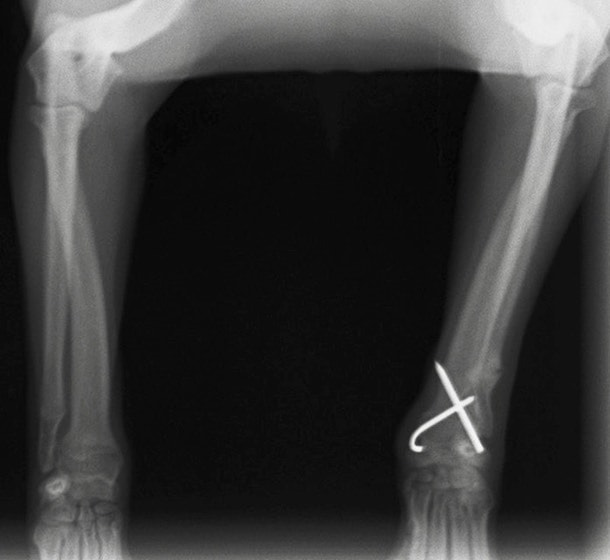

術後レントゲン

他院にて左大腿骨遠位の成長板骨折(salter-harrisⅠ型)が認められており、治療相談を目的として来院。当院にて、キルシュナーワイヤーを用いたピンニングにより骨折部位の整復を行いました。術後の経過は良好で、現在も経過観察中です。

Arthrex社のターゲティングデバイスを用いてピンニングの位置を調整することで、確実な固定を行っています。当院ではこの手術器具以外にも、人の手術にも使用される様々な器具を導入し、手術精度を高め、また医療メーカーと新しい器具の開発、試作にも取り組んでおります。